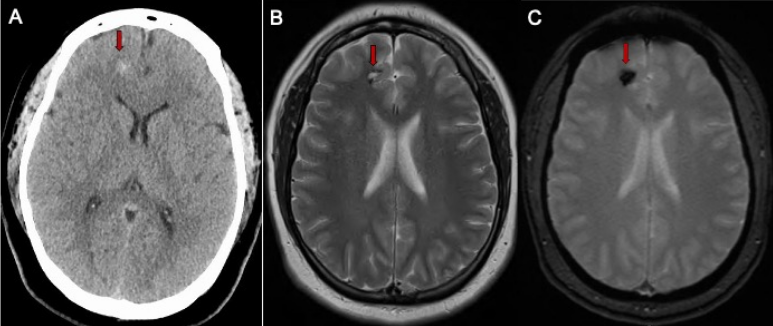

Cerebral cavernous malformations (CCMs) also known as “cavernous hemangiomas,” or simply “cavernomas” are clusters of closely packed abnormal blood vessels encircled by healthy brain tissue. These lesions range in size from less than a quarter of an inch to more than four inches. Unlike brain AVMs, these lesions are low pressure and low flow but still are at risk of leaking blood Read more…